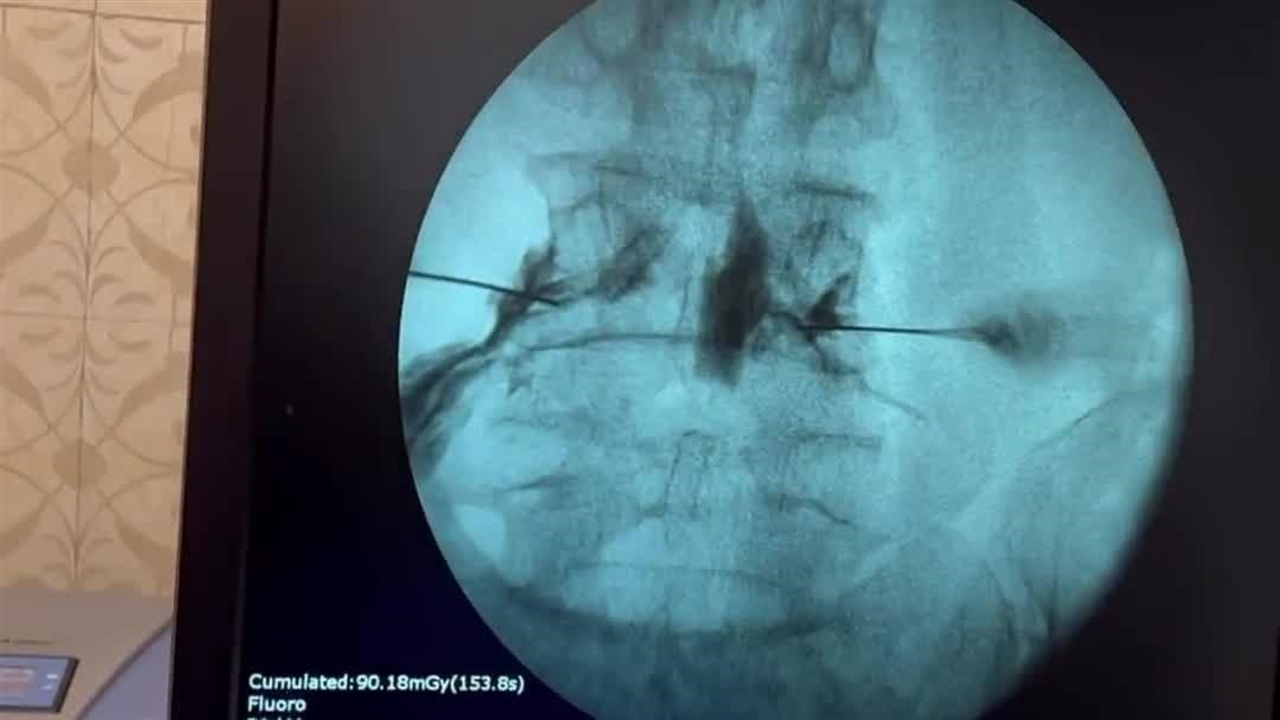

مراجع عزیزم در پاهاشون درد و بی حسی داشتن که علت دردشون تنگی کانال کمر بود.

با توجه به سن بالا ترجیح دادیم براشون عمل بسته دیسک انجام بدیم که یه عمل سرپایی هست

و در درصد بالایی از موارد فرد بدون نیاز به جراحی باز، به زندگی بدون درد برمیگرده ️